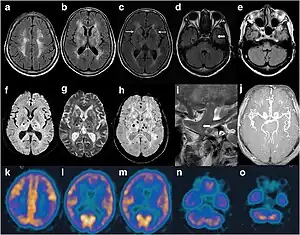

| Cranial imaging of an FFI patient. In the MRI, there are abnormal signals in the bilateral frontoparietal subcortical area. MRA showed smaller distal branches of cerebral arteries. | |

A test that measures the cerebral metabolic rate of glucose by positron emission tomography (PET), referred to as [18F]-FDG-PET, has demonstrated severe hypometabolism of the thalamus bilaterally in FFI and sFI, also in the earliest stages of the disease. This hypometabolism then spreads, eventually impacting most cortical regions.[Cortelli et al. Brain 2006] The complexity and cost of this test currently impedes its use in routine diagnosis.